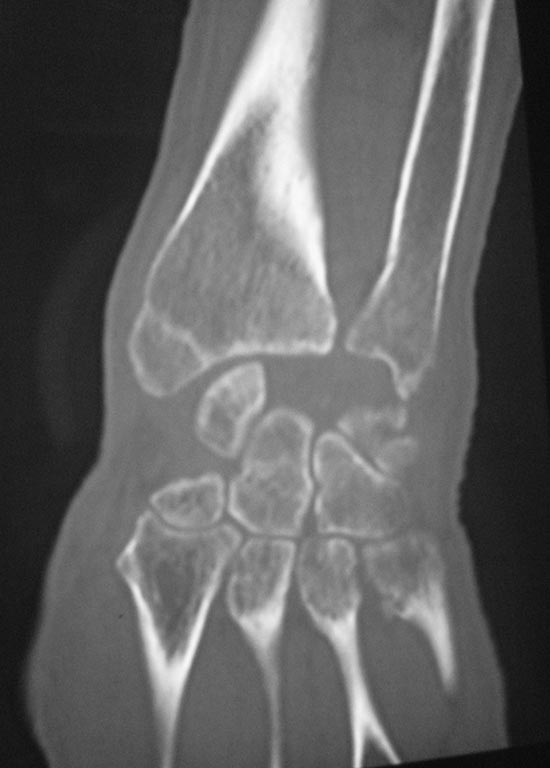

Поступил пациент В, 49 лет. С жалобами: на ограничение движение в правом лучезапястном суставе, на жжение в пальцах правой кисти в ночное время. Анамнез: получил травму 25.12.2015 г. лечили амбулаторно перелом лучевой кости, наложена гипсовая лонгета. После снятие гипса легча не стало. Амбулаторные снимки прилагаются. Выполнили КТ DS: признаки вывиха полулунной кости, срастающийся перелом лучевой кости дистального эпифиза, трехгранной кости. Нужна помощь в тактике лечения.

Вот КТ

Данный пациент сложный. Помимо имеющегося застарелого ладонного вывиха полулунной кости, консолидирующегося внутрисуставного перелома эпифиза лучевой кости, уже сейчас имеется нейропатия срединного нерва. В связи с этим лечение данного пациента откладывать нельзя.